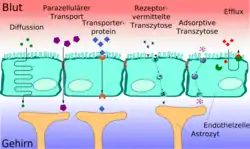

Transportprozesse der Blut-Hirn-Schranke

Die Blut-Hirn-Schranke muss trotz ihrer Funktion als Schutzbarriere auch den Transport von Nährstoffen zum Gehirn, beziehungsweise den Abtransport von Stoffwechselprodukten aus dem Gehirn, gewährleisten. Wasserlösliche Nährstoffe und Peptide überwinden die Blut-Hirn-Schranke im Wesentlichen durch spezifische Transporter oder spezielle Kanäle in der Zellmembran. Die meisten anderen löslichen Verbindungen passieren – wenn überhaupt – diese Barriere durch Diffusion.[11][15]

Parazellulärer Transport

Bei peripheren Kapillaren findet der Stofftransport zu Organen und Muskeln im Wesentlichen durch Fenestrierungen und Intrazellularspalten statt. Bei einem gesunden und intakten zerebralen Endothel sind die einzelnen Endothelzellen untereinander über die Tight Junctions dicht verbunden. Die Kapillargefäße des Gehirns lassen daher hauptsächlich nur einen transmembranen Stofftransport zu, der zudem von den Zellen besser als der parazelluläre Transport geregelt werden kann.[99] Wasser, Glycerin und Harnstoff sind Beispiele für kleine polare Verbindungen, die durch die Tight Junctions der Blut-Hirn-Schranke hindurchdiffundieren können.[100]

Freie Diffusion

Die einfachste Form des Transportes durch die Blut-Hirn-Schranke stellt die freie Diffusion dar. Dieser auch als passiver Transport bezeichnete Austausch kann prinzipiell sowohl durch die Zellmembran der Endothelien als auch durch die Tight Junctions stattfinden. Dabei wird – wie bei jeder Diffusion – ein Konzentrationsausgleich oder der Ausgleich eines elektrochemischen Gradienten angestrebt. Bei der freien Diffusion wird für den Membrantransport keine Energie aus der Zelle benötigt. Der Materialfluss ist proportional zur Konzentration und kann von der Zelle nicht reguliert werden.[101]

Die lipophilen („fettfreundlichen“) Eigenschaften der Zellmembran und ihre dichte Verknüpfung über die Tight Junctions reduzieren die Zahl der Substanzen, die durch Diffusion die Blut-Hirn-Schranke überwinden können, allerdings erheblich. Die Durchlässigkeit der Blut-Hirn-Schranke für ein bestimmtes Molekül steht in direktem Verhältnis zu seiner Lipophilie.[102] Bezüglich der molaren Masse verhält es sich umgekehrt proportional. Das heißt, je lipophiler und kleiner eine Verbindung ist, umso leichter kann sie durch das Endothel hindurch diffundieren.[11] Für die molare Masse eines Moleküls wird als Grenzwert eine maximale Größe von 400 bis 500 g·mol−1 bei einer intakten Blut-Hirn-Schranke angegeben. Moleküle oberhalb dieses Grenzwertes können nicht durch die Blut-Hirn-Schranke diffundieren. Man darf die Blut-Hirn-Schranke allerdings nicht als diskrete Barriere verstehen, die eine bestimmte Molekülgröße komplett zurückhält und einer kleineren vollständig die Diffusion in das Gehirn ermöglicht. Die Diffusionsprozesse an der Blut-Hirn-Schranke sind dynamische Gleichgewichte. Für ein Molekül mit einer Querschnittsfläche von 0,52 nm², was einer molaren Masse von etwa 200 g·mol−1 entspricht, ist die Blut-Hirn-Schranke um den Faktor 100 durchlässiger als für ein Molekül mit einer Fläche von 1,05 nm² (= 450 g·mol−1).[20][103]

Erleichterte Diffusion

Eine spezielle Form der Diffusion durch die Zellmembran der Endothelien ist die erleichterte Diffusion (engl. facilitated diffusion). Lebenswichtige Nährstoffe wie Glucose und viele Aminosäuren sind zu polar und zu groß, um auf den bisher geschilderten Transportwegen in ausreichender Menge dem Gehirn über die Blut-Hirn-Schranke zur Verfügung gestellt zu werden. Für diese Moleküle gibt es in der Zellmembran ein spezielles Transportsystem: den sogenannten Carrier-vermittelten Transport. Beispielsweise wird die D-Glucose über den GLUT-1-Transporter in das Gehirn transportiert. Die Dichte der GLUT-1-Transporter ist auf der abluminalen Seite der Endothelien viermal höher als auf der luminalen, das heißt der zum Blut hin gerichteten, Seite.[120] Der Transport wird nur durch ein Konzentrationsgefälle ermöglicht und benötigt selbst keine Energie.

Aktiver Transport

Bei den zuvor beschriebenen passiven Arten des Transportes durch das Endothel gelangen die Moleküle ohne zusätzlichen Bedarf an Energie zum Gehirn, beziehungsweise vom Gehirn weg. Sie folgen dabei dem jeweiligen Konzentrationsgefälle. Mit aktiven Transportern, sogenannten „Pumpen“, ist ein Transport auch gegen einen Konzentrationsgradienten möglich. Dabei wird allerdings direkt oder indirekt Energie in Form von Adenosintriphosphat benötigt.[99] Findet der aktive Transport vom Blut zum Gehirn statt, so spricht man von Influx („Einströmen“). In umgekehrter Richtung spricht man von Efflux („Abfluss“).

Vesikulärer Transport

Rezeptorvermittelte Transzytose

Für den Transport ausgewählter großer Moleküle gibt es die rezeptorvermittelte Transzytose. Spezielle Rezeptoren, die durch die Zellmembran nach außen in das Lumen ragen, sind für die Erkennung der aufzunehmenden Substanzen zuständig.[1] So gelangt beispielsweise das 75,2 kDa schwere und aus 679 Aminosäuren bestehende Transferrin aus dem Blut in die extrazelluläre Flüssigkeit des Gehirns.[146] Die im Lumen befindlichen Rezeptoren werden nach der Anbindung des Transferrins internalisiert, das heißt in das Zellinnere eingeschleust. Über coated pits wird es dann auf die andere Seite der Zelle (abluminale Seite) transportiert und ausgeschleust. Mit dem gleichen Mechanismus wird über den LDL-Rezeptor der Transport von Low Density Lipoprotein zum Gehirn ermöglicht, um dort daraus Cholesterol produzieren zu können.[112][147] Auch Insulin[148] und andere Peptidhormone sowie Zytokine gelangen auf diesem Weg zum Gehirn.[1]

Adsorptionsvermittelte Transzytose

Bei der adsorptionsvermittelten Transzytose (adsorptive-mediated transcytosis, AMT) bewirken elektrostatische Wechselwirkungen zwischen der durch Glykoproteinen negativ geladenen Zelloberfläche und positiv geladenen Molekülen (Kationen) einen Transport durch das Zytoplasma der Endothelien.[149] Diese Form des Transportes wird auch als kationischer Transport bezeichnet.[150] Eine positive Ladung weisen beispielsweise Peptide und Proteine auf, deren isoelektrischer Punkt im Basischen liegt.[151] Die kationische Transzytose durch das Endothel der Blut-Hirn-Schranke ermöglicht einen höheren Grad des Stofftransportes als die rezeptorvermittelte Transzytose.[152]